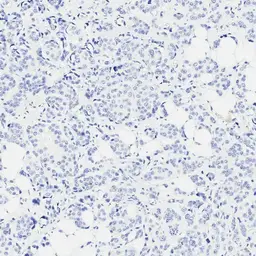

Optimal staining result of the human TNBC, tissue core no. 7, following the vendor recommended protocol settings.

No staining reaction is observed. The tumour was categorized as CPS Low (<10).